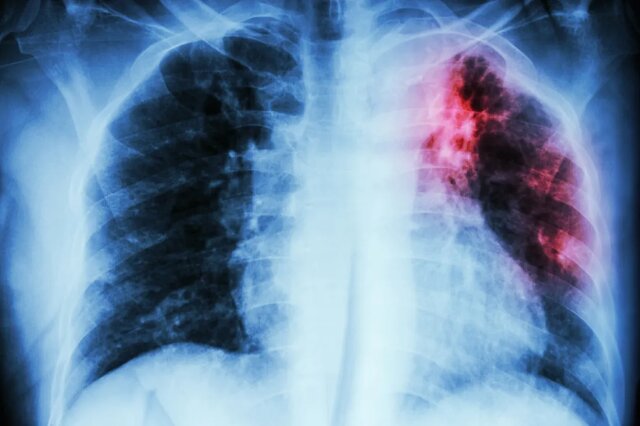

ایسنا/خوزستان سل (Tuberculosisیا TB) یک بیماری عفونی شایع و کشنده است که توسط گونه‌های مختلف مایکوباکتری و بیشتر توسط «مایکوباکتریوم توبرکلوزیس» ایجاد و انتقال آن با قطره‌های تنفسی از فرد بیمار انجام می‌شود.

وی افزود: سل یک بیماری عفونی واگیردار است که از دیرباز در کشورهای گوناگون جهان وجود داشته و در طول تاریخ، جان بسیاری از انسان‌ها را گرفته است. با وجود فعالیت‌ها و اقدامات موثری که در طول دهه‌های گذشته انجام شده است همچنان سل به عنوان یک معضل جهانی به شمار می‌رود و کنترل و مراقبت آن با چالش‌های جدی روبه‌رو است.